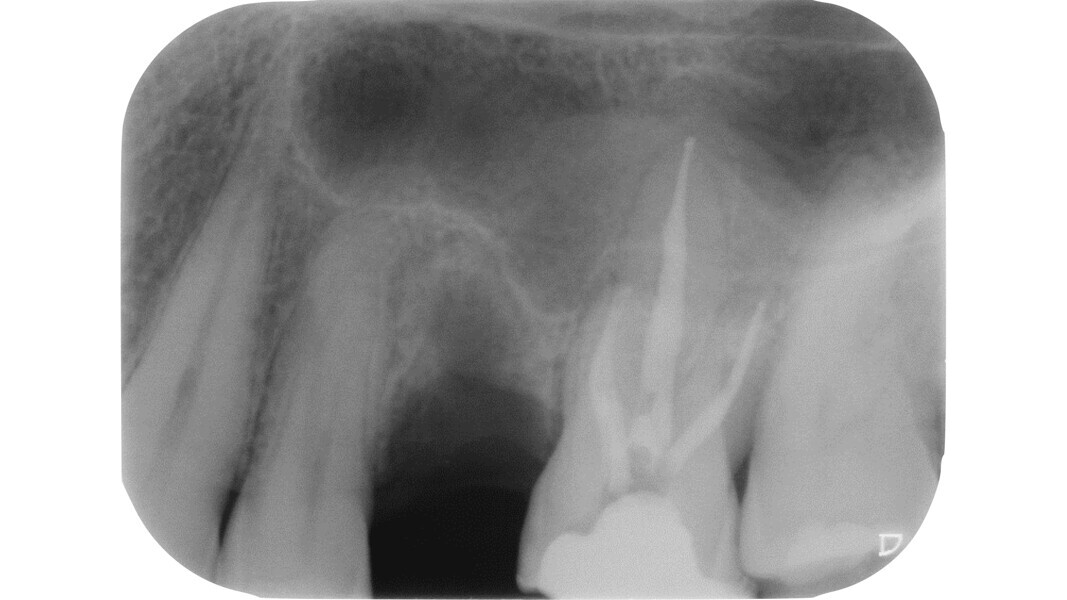

Le principe du diamant fait référence à l’utilisation d’un certain type de fraise diamantée pour la phase de pénétration, en particulier dans les molaires supérieures et inférieures, ainsi que dans les prémolaires supérieures biradiculées. Deutsch8–9 associe des mesures morphologiques à la relation entre la surface occlusale, la hauteur, la position du plafond et du plancher de la cavité dans les dents pluriradiculées. Dans ces éléments, le plafond de la cavité pulpaire est situé au niveau de la JAC.

Dans les molaires, la distance entre la pointe d’une cuspide et le plafond de la cavité pulpaire est d’environ 6,3 mm, tandis que dans les prémolaires supérieures, elle est de 6,94 mm. La cavité pulpaire a une hauteur d’environ 1,5 à 2 mm et la distance moyenne entre le plancher de la cavité et la furcation est d’environ 3 mm (Tableau 1) (Fig. 13).